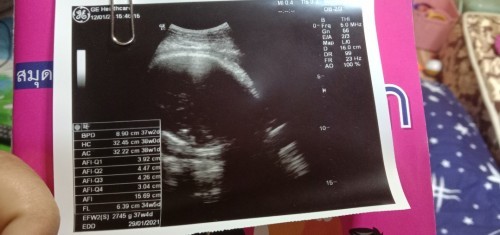

ในใบซาวด์ 37 w กำหนดคลอด 29/1/64 แต่ในสมุดหมอลง 35 w กำหนดคลอด 12/2/64 เราควรเชื่ออันไหนดีค่ะ งง

ในใบซาวน์จะประเมินวันคลอดจากขนาดและน้ำหนักตัวเด็กค่ะ ถ้าเป็นคุณหมอจะนับจากประจำเดือนครั้งสุดท้ายค่ะแม่

ใบซาวเป็นการวัดขนาดของเบบี๋แล้วประมวลผลออกมาคร่าวๆโดยประมาณครับ คลอด12/2/จะใกล้เคียงกว่าครับ